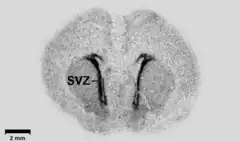

Autoradiography: A tissue section affixed to a microscope slide or a membrane such as a Northern blot or a hybridized slot blot can be placed against x-ray film or phosphor screens to acquire a photographic or digital image. The density of exposure, if calibrated, can supply exacting quantitative information.

Micro-autoradiography: A tissue section, typically cryosectioned, is placed against a phosphor screen as above.